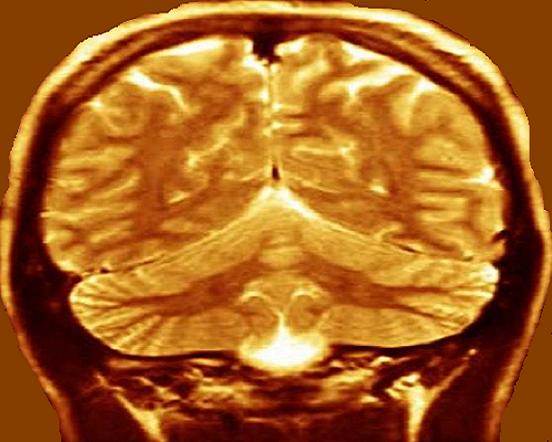

MRI Provided by:

Scott Camazine